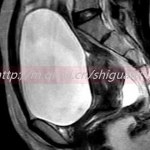

试管婴儿技术规范的要求及适应症:①年龄:女方一般不超过40岁,男方不超过55岁。如需赠卵的妇女年龄可放宽到50岁,男性可在60岁。②必须身体健康,没有不适应怀孕的急性病和慢性病、无遗传性疾病、无精神类疾病及性传播性疾病。试管婴儿技术较适合以下几种情况:输卵管因素的不孕;不明原因的不孕不育;男性不育;免疫性不孕;子宫内膜异位症;其他常见的如子宫肌瘤,卵巢囊肿等;卵巢功能衰竭。。体外受精-胚胎移植技术每一周期的临床妊娠率约为35%-45%。这项技术的关键在于,必须准确判断母体排卵时间,和安全无损伤的获取成熟卵子;必须创造一个适合卵子和精子在体外能够很好的结合与成活的条件,也就是要体外授精并孕育三天左右;必须高超准确无误地把授精卵重新种植到母体的子宫内膜上。其中任何一步都需要先进的科学技术、不能滥用。